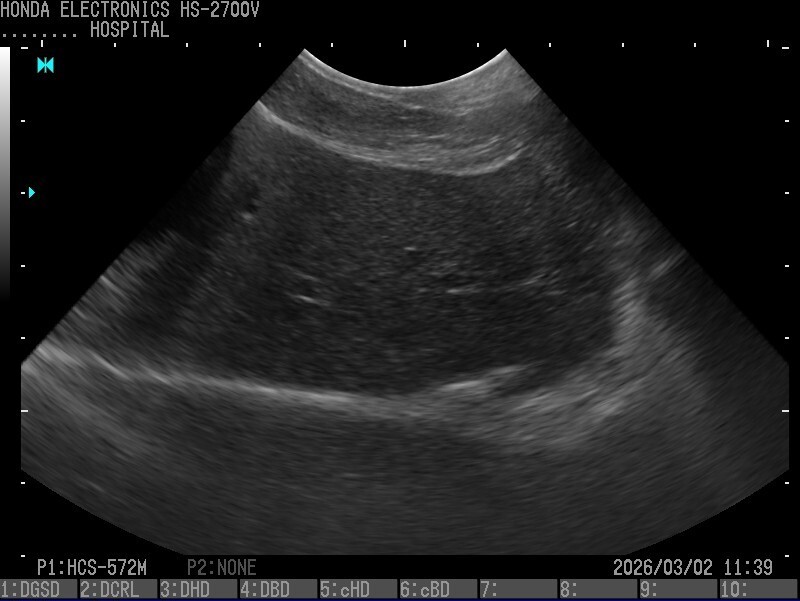

超音波画像

超音波診断画像

胆嚢、肝臓(犬)

1.胆嚢、肝臓(パピヨン・10歳)

プローブ:HCS-572M

H-res:Detail2